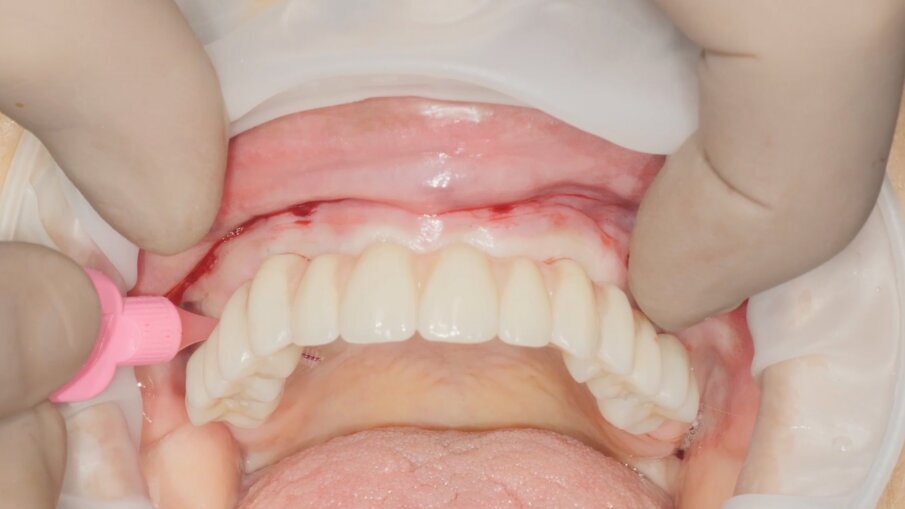

Veniamo quindi al posizionamento della protesi mediante carrier, a sua volta ancorato agli stessi punti di fissaggio della dima base. È significativo osservare come la stabilizzazione della sola vite palatale consenta l’allineamento perfetto tra i sistemi di fissaggio (Fig. 22), mentre il dettaglio mostrato in Fig. 24 illustra efficacemente come prima della cementazione della protesi l’accoppiamento e la centratura del foro protesico appaiano perfetti, confermando quindi come l’obiettivo di alloggiamento della protesi nella sede prestabilita sia stato colto. Per la fase di cementazione con cemento duale si è prestata attenzione alla realizzazione di un foro aggiuntivo per permettere al materiale di raggiungere gli abutment. I fori di accesso alle viti vengono tappati con filo di teflon (Figg. 25, 26) ed è a questo punto possibile andare a fissare la protesi e rimuovere il sistema carrier (Fig. 27). Lasciamo la dima in posizione, così che nell’eventualità in cui un abutment non dovesse essere stato cementato correttamente, ci riserviamo la possibilità di riprendere il posizionamento strategico dell’intero sistema Pcube, intercettando possibili impedimenti alle manovre di finalizzazione del caso.

Nella fase di controllo finale possiamo apprezzare come i rapporti di intercuspidazione programmati siano stati perfettamente rispettati (Fig. 28), senza necessità di ricorrere a procedure di auto-centratura della protesi, grazie ad una attenta pianificazione digitale. Eseguiamo una scansione con scan abutment in posizione prima di procedere con la rimozione della dima base e il fissaggio della protesi (Figg. 29-31). Controlliamo le possibilità di mantenimento igienico tenendo conto che, trattandosi di un intervento flapless, non abbiamo le problematiche legate alla gestione di una linea di incisione (Fig. 32). La Fig. 33 mostra la corretta guarigione dei tessuti quindici giorni dopo il trattamento. Eseguiamo un controllo radiografico mirato a verificare il corretto alloggiamento di tutti gli impianti e della protesi (Fig. 33), dove possiamo vedere la struttura di rinforzo in fibra di vetro.